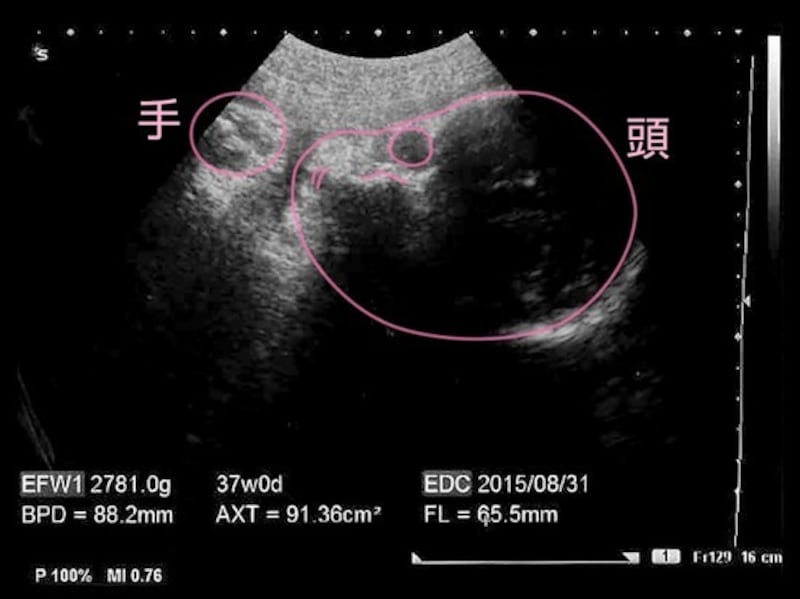

妊娠37週目の胎児の発達

- 妊娠37週目:受精から245~251日目

- 胎児の大きさ:頭殿長(座高)が48~49cm

- 胎児の体重:2200~3100gほど

- 母体の変化:正期産の時期に。前駆陣痛を感じることも

赤ちゃんは背を丸めたスタイルをとっています。手足を動かすスペースはあまりないもののモゾモゾと動いていますが、大きな動きがないだけに、お母さんには胎動が少なくなったと感じられるかもしれません。